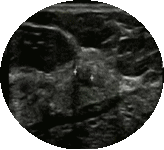

异常乳腺超声图

BI-RADS分级将乳腺病变分为0~6级,级别越高,恶性可能性越大。

左图显示左乳小结节,病理为良性病变